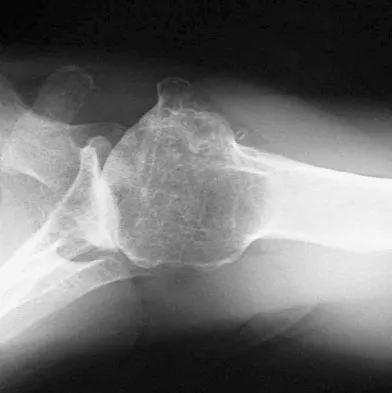

Figures 12a and 12b show the radiographs of a 50-year-old patient who reports acute knee pain after sustaining a twisting injury while playing tennis. Examination is unremarkable. The next most appropriate step in management should consist of

Explanation

The radiographs show localized diffuse cortical thickening that is characteristic of melorheostosis. The condition may be monostotic or it may involve many bones in one extremity (monomelic) in the distribution of a sclerotome. Bone scans will show increased uptake at the site or sites of skeletal involvement. Long tubular bones are most commonly involved. Melorheostosis is usually asymptomatic and requires no treatment. On rare occasions, there may be associated soft-tissue contractures. Dorfman H, Czerniak B: Bone Tumors. St Louis, MO, Mosby Inc, 1998, pp 1105-1107. Campbell CJ, Papademetriou T, Bonfiglio M: Melorheostosis: A report of the clinical, roentgenographic, and pathological findings in fourteen cases. J Bone Joint Surg Am 1968;50:1281-1304.